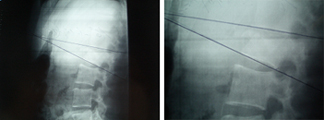

Fractura vertebral por estallido, inestable,

con un índice sagital (cifosis) no tolerable

Imagen de la fractura y del postoperatorio con una reducción anatómica

y una visión de la espalda de la paciente con incisiones puntiformes

a las 48 horas de la intervención, en el momento de recibir el alta.